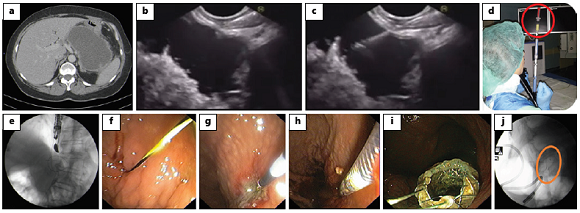

Fig. 1: EUS-guided transmural drainage using a standard approach. a, b Computed tomography (a) and EUS (b) images obtained 6 weeks after a severe pancreatitis episode showing a large homogeneous fluid collection between the pancreatic corpus and the stomach, with a well-defined wall; the findings were consistent with a pseudocyst. c Via a transgastric approach, puncture of the collection using 19-G fine-needle aspiration was performed. d Aspiration of purulent fluid from the collection. e, f A 0.035-inch guidewire is introduced through the needle (e) and is coiled within the pseudocyst under fluoroscopic guidance (f). g The fistulous tract is dilated using a 10-Fr cystostome. h Placement of a lumenapposing metal stent (BCF covered Diabolo shape, Hanarostent®). i Proximal flange of the stent deployed in the stomach. j Stent deployment confirmed by fluoroscopy. EUS, endoscopic ultrasound.

The standard procedure should be performed in a room with fluoroscopic imaging, as both ultrasonography and fluoroscopy guidance are needed for stent deployment. A therapeutic linear echoendoscope with a working channel of 3.7-3.8 mm is required in order to enable the insertion of stents or a nasocystic catheter.

1. Begin the procedure with location of the collection and its contact zone with the gastric/duodenal lumen; the distance between the collection and the gastroduodenal wall should not exceed 10 mm in order to smooth the procedure and avoid adverse events [22]

2. Assess for interposed vessels by Doppler mode and determine the optimal site for puncture

3. Puncture the collection using 19-G fine-needle aspiration (a sample may be aspirated and sent for laboratory analysis, such as microbiology); a 0.035-inch guidewire is introduced through the needle and is coiled within the pseudocyst under fluoroscopic guidance

4. Dilate the tract sequentially using endoscopic retrograde cholangiopancreatography cannulas, Soehendra biliary dilators or 6- to 15-mm over-the-wire biliary balloons; alternatively, a 10-Fr cystostome or a needle knife catheter may be used for dilation

5. For double pigtail plastic stent (PS) placement, introduce an additional guidewire through the fistulous tract and place the two PS, usually of a calibre of 7-10 Fr

6. For fully covered self-expandable metallic stent or lumen-apposing metal stent (LAMS) placement, introduce the stent delivery device through the tract over the wire and deploy the stent

Using a Cautery-Enhanced LAMS (Fig. 2)